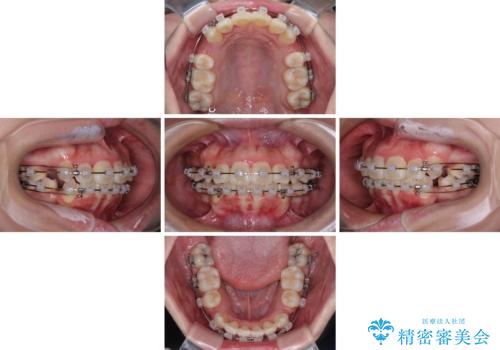

- クリアブラケット

- 2年

- 10-30回